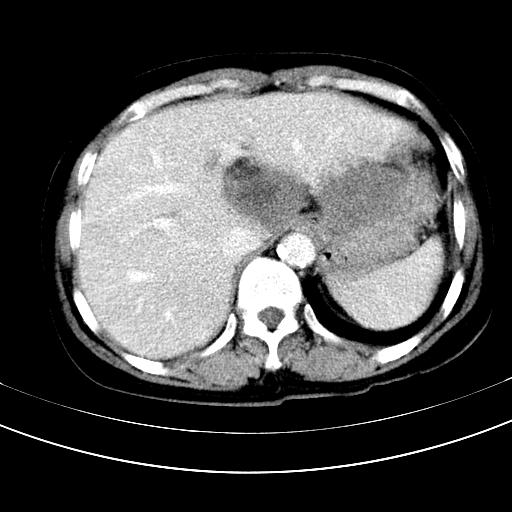

标题: CT12767:肝脏病变请会诊

补充强化片

胃内见充盈缺损,建议行胃镜病理检查,如果胃内无占位,则肝内考虑左叶、尾叶为包膜型肝癌,如有则考虑为转移瘤

胃内的充盈缺损,当时让患者俯卧位在扫描一下就 好了,当然最好是增强扫描,肝脏的病灶平扫很难定性,可以考虑是肝癌·血管瘤·转移瘤!

胃内见充盈缺损,建议行胃镜病理检查,如果胃内无占位,则肝内考虑左叶、尾叶为包膜型肝癌,如有则考虑为转移瘤,左侧肾上腺 明显增大,成结节改变,本人考虑转移瘤可能性大。

胃内的充盈缺损因胃壁不厚,我个人考虑为胃内残留物。肝左叶及尾叶病灶,我首先考虑血管瘤,其次为肝癌。(尾叶的更低密度区太规整)

肝脏左叶和尾叶均见略低密度影,尾叶病变内见坏死?其边界清晰,形态规整1血管瘤,2肝癌待排

胆囊内见一略高密度影,息肉?

1.肝左叶及尾叶占位建议增强2.肝硬化

肝脏左叶和尾叶均见略低密度影,尾叶病变内见坏死?其边界清晰,形态规整1血管瘤,2肝癌待排3建议增强。

胃内充盈缺损考虑为胃内存留物,肝左叶和尾状叶两个病灶,均为低密度,建议增强。

考虑:胃体小弯侧胃癌(或平滑肌瘤恶化或平滑肌肉瘤)伴肝转移,左侧肾上腺转移不除外.

胃内充盈缺损考虑为肿瘤,肝尾叶及左叶肿块考虑转移瘤

胃癌肝内转移及肾上腺转移。

不强化不好说!肝内像是血管瘤,胃底考虑间质瘤。脾静脉还有曲张的可能。本病例必须强化明确!

胃窦部占位伴肝及左肾上腺转移可能大,建议增强扫描。

肝脏左叶和尾叶均见略低密度影,尾叶病变内见坏死?其边界清晰,形态规整1血管瘤,2肝癌待排3建议增强或结合临床及超声与实验室检查

肝左叶及尾叶低密度灶,增强有渐进性明显强化,考虑血管瘤。胃内“充缺”首先要排除异物(食物),变换体位可鉴别。增强时机抓的不好,还应该有延时像。

谢谢楼主的增强片子,平扫没发现左侧肾上腺的问题很不好意思,可惜片子只有门脉期,所以还只有猜,肝脏的病灶在门脉期部分强化,首先考虑为血管瘤(其他的用一种病不好解释)胃要喝水就好了现在不好说是否有问题,左肾上腺的问题考虑是肿瘤。

做了增强后,可以明确胃是没有肿瘤的,肾上腺也没有肿瘤.肝左叶的病灶首先考虑血管瘤,应该再延迟,肝尾状叶的病灶仍不能排除肝癌的可能性.